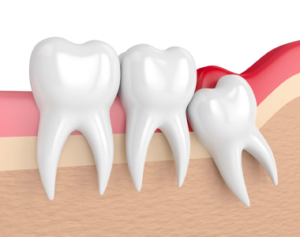

Understanding Your Wisdom Teeth As you grow, your mouth undergoes many changes. One significant change…